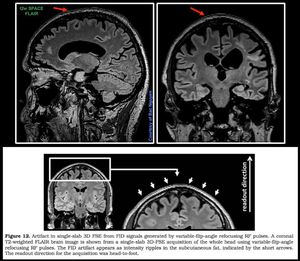

You noticed this artifact on SPACE sequence? Can be seen clearly on t2w SPACE flair. I’ve been looking for the answer and finally found out a while ago. I can't remember where I found the figure showing here. Nevertheless, it’s a FID artifact appears as intensity ripples in the subcutaneous fat. Does this bother you? Doesn’t bother me, it’s not in the anatomy and I really need these SPACE sequences.#Siemens_MRI #mri #optimising